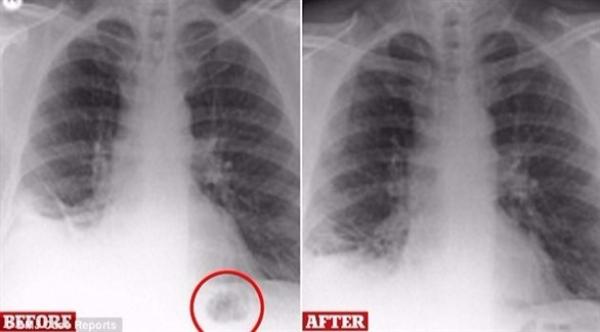

اعتقد الأطباء أنه مصاب بالسرطان.. فعثروا على شيء غريب في رئته